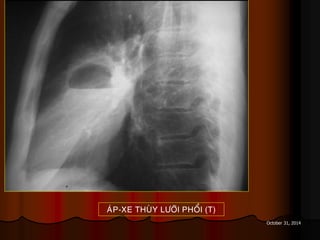

AÙP-XE THUØY LÖÔÕI PHOÅI (T)

October 31, 2014 AÙP-XETHUØY LÖÔÕI PHOÅI (T)